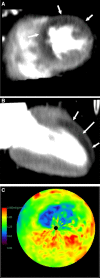

Myocardial ischemia is caused by a mismatch between myocardial oxygen consumption and oxygen delivery in coronary artery disease (CAD). Stratification and decision-making based on ischemia improves the prognosis in patients with CAD. Non-invasive tests used to evaluate myocardial ischemia include stress electrocardiography, echocardiography, single-photon emission computed tomography, and magnetic resonance imaging. Invasive fractional flow reserve is considered the reference standard for assessment of the hemodynamic significance of CAD. Computed tomography (CT) angiography has emerged as a first-line imaging modality for evaluation of CAD, particularly in the population at low to intermediate risk, because of its high negative predictive value; however, CT angiography does not provide information on the hemodynamic significance of stenosis, which lowers its specificity. Emerging techniques, e.g., CT perfusion and CT-fractional flow reserve, help to address this limitation of CT, by determining the hemodynamic significance of coronary artery stenosis. CT perfusion involves acquisition during the first pass of contrast medium through the myocardium following pharmacological stress. CT-fractional flow reserve uses computational fluid dynamics to model coronary flow, pressure, and resistance. In this article, we review these two functional CT techniques in the evaluation of myocardial ischemia, including their principles, technology, advantages, limitations, pitfalls, and the current evidence.